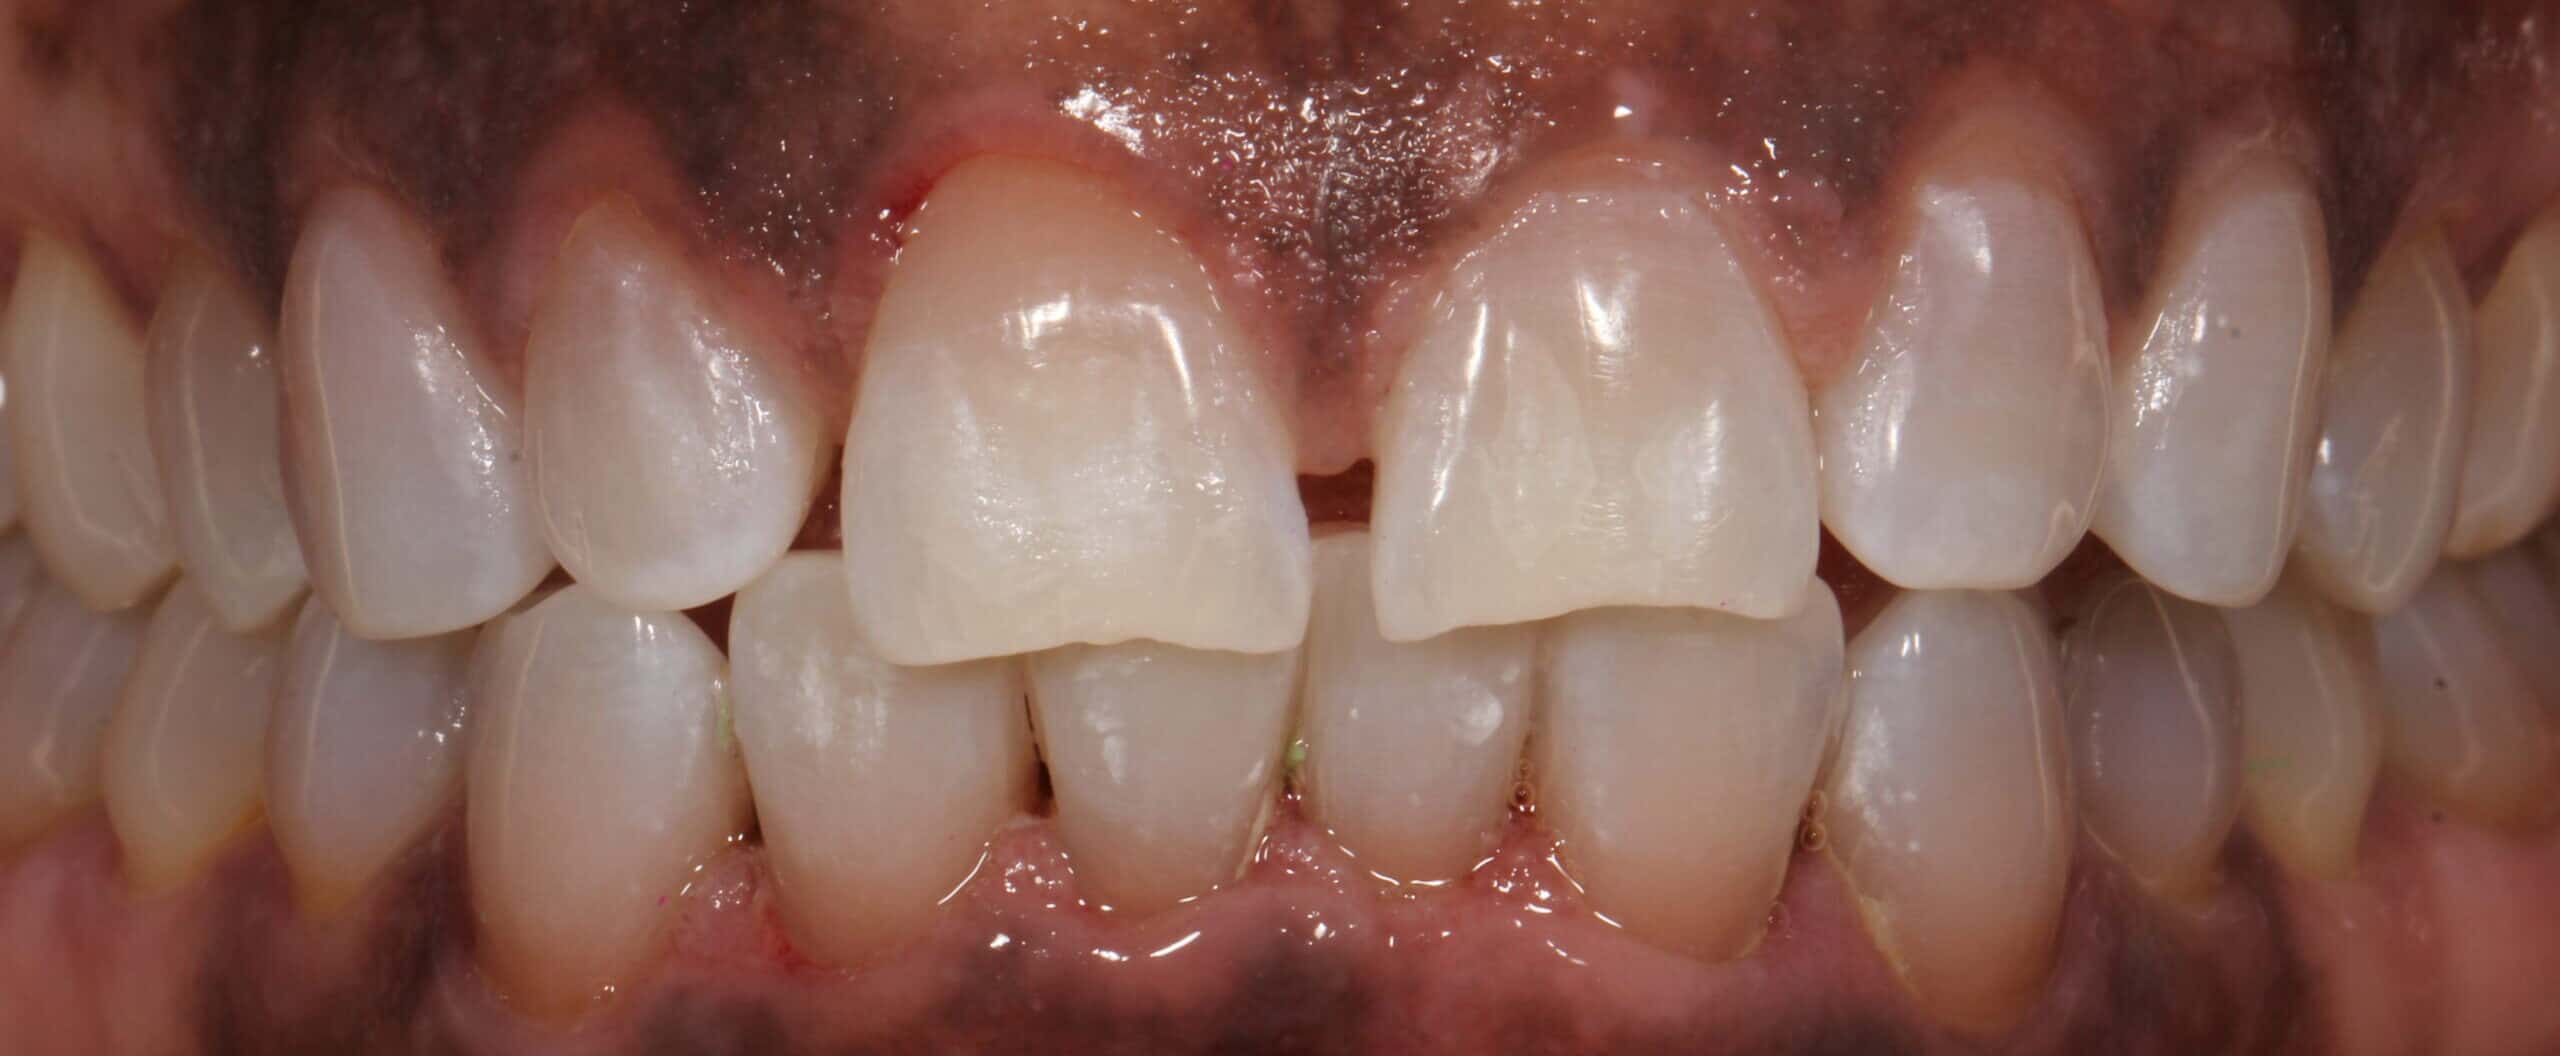

Does teeth cleaning remove yellow?

Your teeth will certainly look brighter and whiter after a deep clean, because tartar build-up takes on a yellowish hue. As the removal of plaque and tartar is a primary focus of the procedure, it will have an immediate positive effect on the overall look of your smile. However, if you’re looking for markedly whiter results you’ll need to book in for a whitening treatment in order to achieve them. Tooth whitening is one of the easiest and most popular cosmetic dentistry procedures we offer, and the results can be nothing short of dramatic.